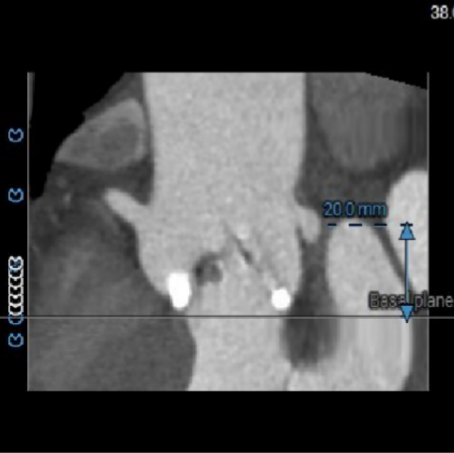

主动脉根部CTA:

ANNULUS

术前考虑右侧股动脉为主入路,左侧为辅助入路。非横位心,主动脉弓角度、宽度尚可,预估输送器过弓难度适宜,跨瓣难度适宜,术中必要时采用Snare辅助。左右冠脉开口高度可,左冠切线角度测量瓣叶大于LCA开口下缘到根部距离,结合瓦氏窦及STJ尺寸预估,冠脉风险适中,建议术中密切关注左冠灌注情况。外周入路走行适宜,腹主中下端和左右髂总散在钙化,血管内径尚可,血管内壁存在不规则纤维增厚和钙化斑,入路穿刺规范操作,小心通过,避免入路血管损伤及相关并发症。重度钙化二叶式病变重度主动脉瓣狭窄,其瓣口面积小,瓣口限制明显,术中瓣膜锚定难度较大,瓣膜植入受二叶瓣瓣叶及团块状钙化挤压存在移位及少量偏多瓣周漏风险,为避免手术并发症,手术预装AV26瓣膜,根据20mm球囊预扩结果选择瓣膜型号,计划瓣膜瓣上3mm开始释放。